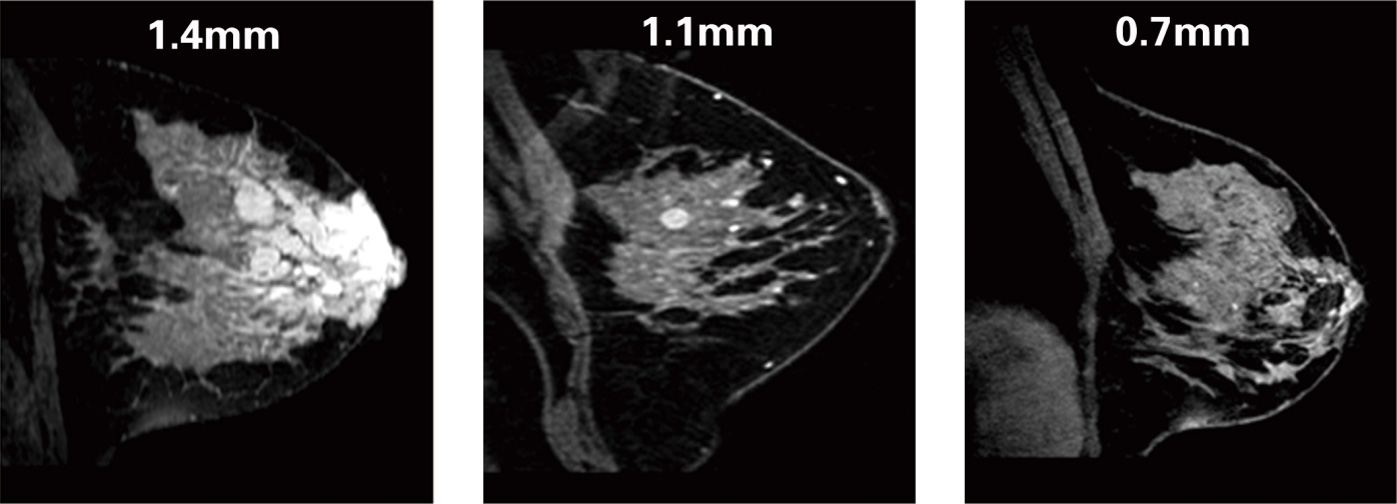

在冠狀面、矢狀面和橫斷面均能提供各向同性0.7mm層厚的分辨率。

不同層厚下的影像